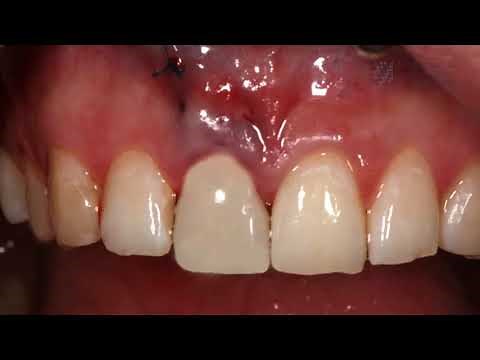

Front tooth extraction with immediate implant and temporary

175.6K views

May 26, 2022

YouTube

Intermountain Smiles